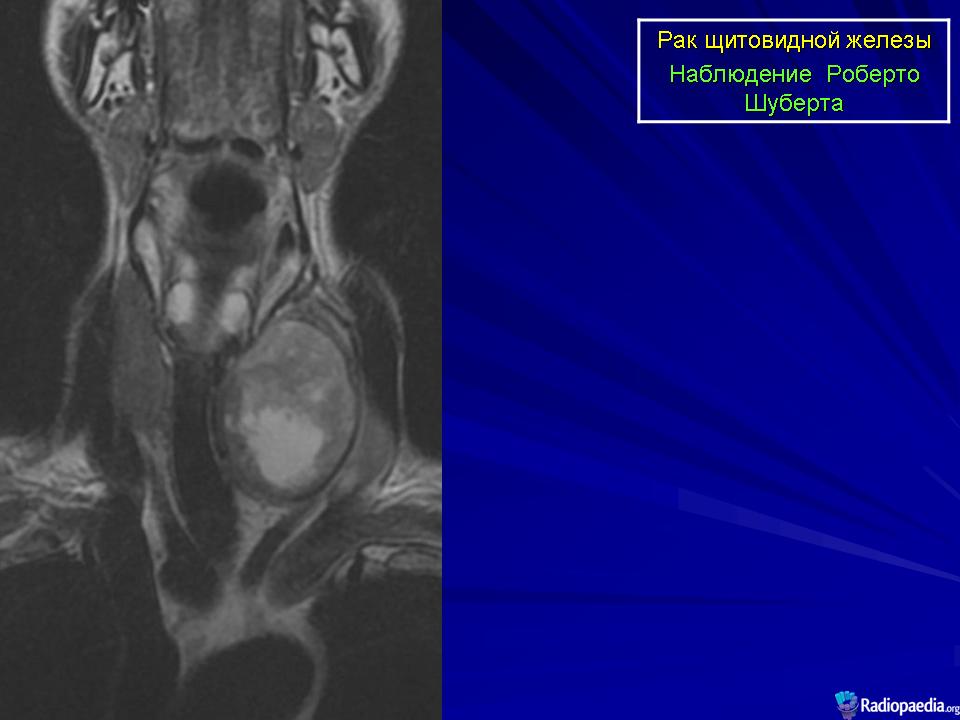

Онкология. ОГК. Опухоли щитовидной железы. +

Опухоли щитовидной железы